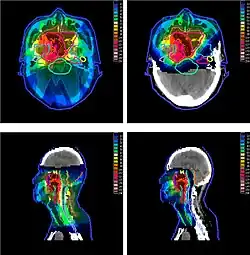

Irradiation of nasopharyngeal carcinoma by photon (X-ray) therapy (left) and proton therapy (right)

The figure at the right of the page shows how beams of X-rays (IMRT; left frame) and beams of protons (right frame), of different energies, penetrate human tissue. A tumor with a sizable thickness is covered by the IMRT spread out Bragg peak (SOBP) shown as the red lined distribution in the figure. The SOBP is an overlap of several pristine Bragg peaks (blue lines) at staggered depths.

Megavoltage X-ray therapy has less "skin sparing potential" than proton therapy: X-ray radiation at the skin, and at very small depths, is lower than for proton therapy. One study estimates that passively scattered proton fields have a slightly higher entrance dose at the skin (≈75%) compared to therapeutic megavoltage (MeV) photon beams (≈60%).[3] X-ray radiation dose falls off gradually, needlessly harming tissue deeper in the body and damaging the skin and surface tissue opposite the beam entrance. The differences between the two methods depends on:

• Width of the SOBP

• Depth of the tumor

• Number of beams that treat the tumor

The X-ray advantage of less harm to skin at the entrance is partially counteracted by harm to skin at exit point.

Since X-ray treatments are usually done with multiple exposures from opposite sides, each section of skin is exposed to both entering and exiting X-rays. In proton therapy, skin exposure at the entrance point is higher, but tissues on the opposite side of the body to the tumor get no radiation. Thus, X-ray therapy causes slightly less damage to skin and surface tissues, and proton therapy causes less damage to deeper tissues in front of and beyond the target.[5]